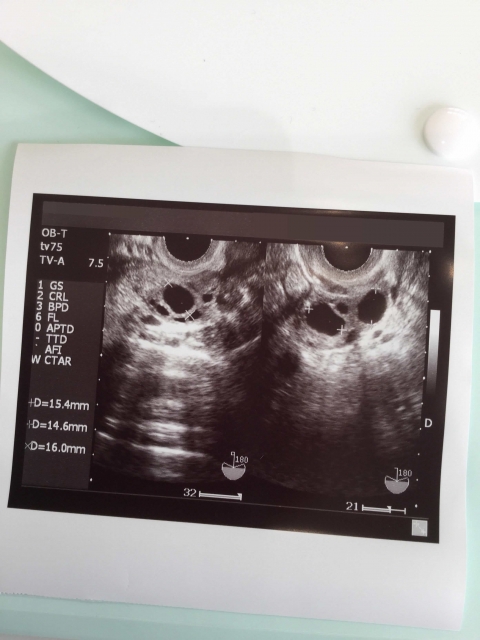

そもそも不妊は病なのだろうか。「医療として」体外受精のような技術を使って「治療」することがふさわしいことなのか。1978年世界で初めて試験管ベービーが誕生した時、生命倫理をめぐり大きな論争がまきおこった。ところが、いつのまにか「不妊治療」は「通常医療」となってしまった。

しかし、これは本来の医療とは本質を異にするものだ。「不妊治療」の目的は唯一出産にいたることであり、厳密な成功率は15〜20%だ。それ以外の場合、多くの人にとって、施された「治療」はすべて無意味なものとなる。無意味なばかりか、その過程で安易でひどい命の切り捨てが進む。当事者に残される費用、仕事や生活、心と身体全般への負担や傷も大きい。

夫以外の男性精子を使った場合、遺伝上の父と育ての父が違うことを知ったときの子どもの苦悩。受精卵の取り違えとその結果行われる中絶。体外受精の際に子宮に戻さなかった「余剰胚」の研究への利用の是非など。さまざまな問題が浮上してきた。体外受精が実際に使われるようになったのは80年代だが、本格的な調査、報道、社会問題化がなされるようになったのは30年以上たってからのこと。